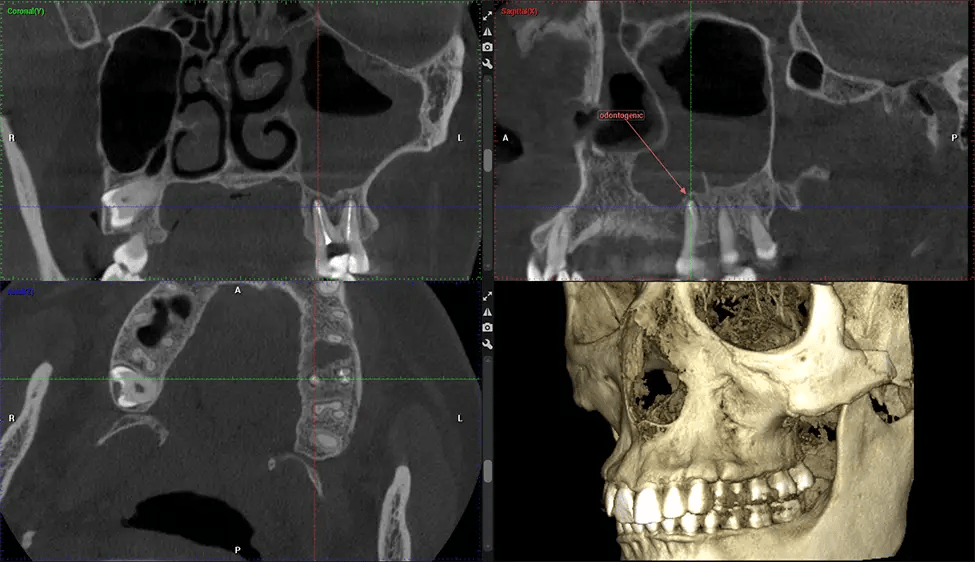

Cone Beam Computed Tomography (CBCT) is an advanced imaging technique used in dentistry and maxillofacial surgery to obtain detailed 3D images of the oral and maxillofacial structures. At Dr G Dental Studio, our CBCT scanners utilize a cone-shaped X-ray beam and a specialized detector to capture images from different angles. A computer then combines these images to create a 3D representation of the patient’s oral anatomy.

This 3D scan, called cone beam computed tomography, gives your dentist a more complete image of your oral anatomy and disease processes than a traditional X-ray. Unlike conventional X-rays, which capture a 2D image of your mouth from various angles, a 3D scan takes multiple digital X-rays for one image. It provides a complete view of your jaw, teeth, nerves, and soft tissues. This enhanced view allows dentists to detect minor issues not visible in traditional 2D scans, such as impacted wisdom teeth or bone fractures in the sinus cavity.

There are many benefits to using CBCT technology, especially compared to the traditional 2D X-ray format. One of the most significant advantages of CBCT scans is that they provide much more information than traditional X-rays. A scan lets your dentist see images from all angles of your jaw and mouth, including your sinuses, nasal cavity, cheekbones, and other surrounding areas. This added information helps your dentist craft a comprehensive treatment plan that addresses all aspects of your oral health.

The patient is first positioned in the CBCT scanner, which typically consists of a rotating arm that houses the X-ray source and a detector. The patient’s head is immobilized to ensure accurate image capture. The X-ray source and detector rotate around the patient’s head, capturing various X-ray images from multiple angles. As the X-ray source rotates, it emits the cone-shaped X-ray beam towards the detector. The detector captures the X-ray images, which are then processed by the CBCT software.

After the scanning process, the captured X-ray images are processed by the CBCT software, which applies algorithms to reconstruct a detailed 3D image of the scanned area. The software compiles these individual X-ray images and creates a digital 3D representation of the patient’s anatomy. The reconstructed 3D CBCT image can be viewed and analyzed by the dentist or radiologist. This image can be manipulated, rotated, and zoomed in or out to examine specific structures and evaluate the patient’s condition.